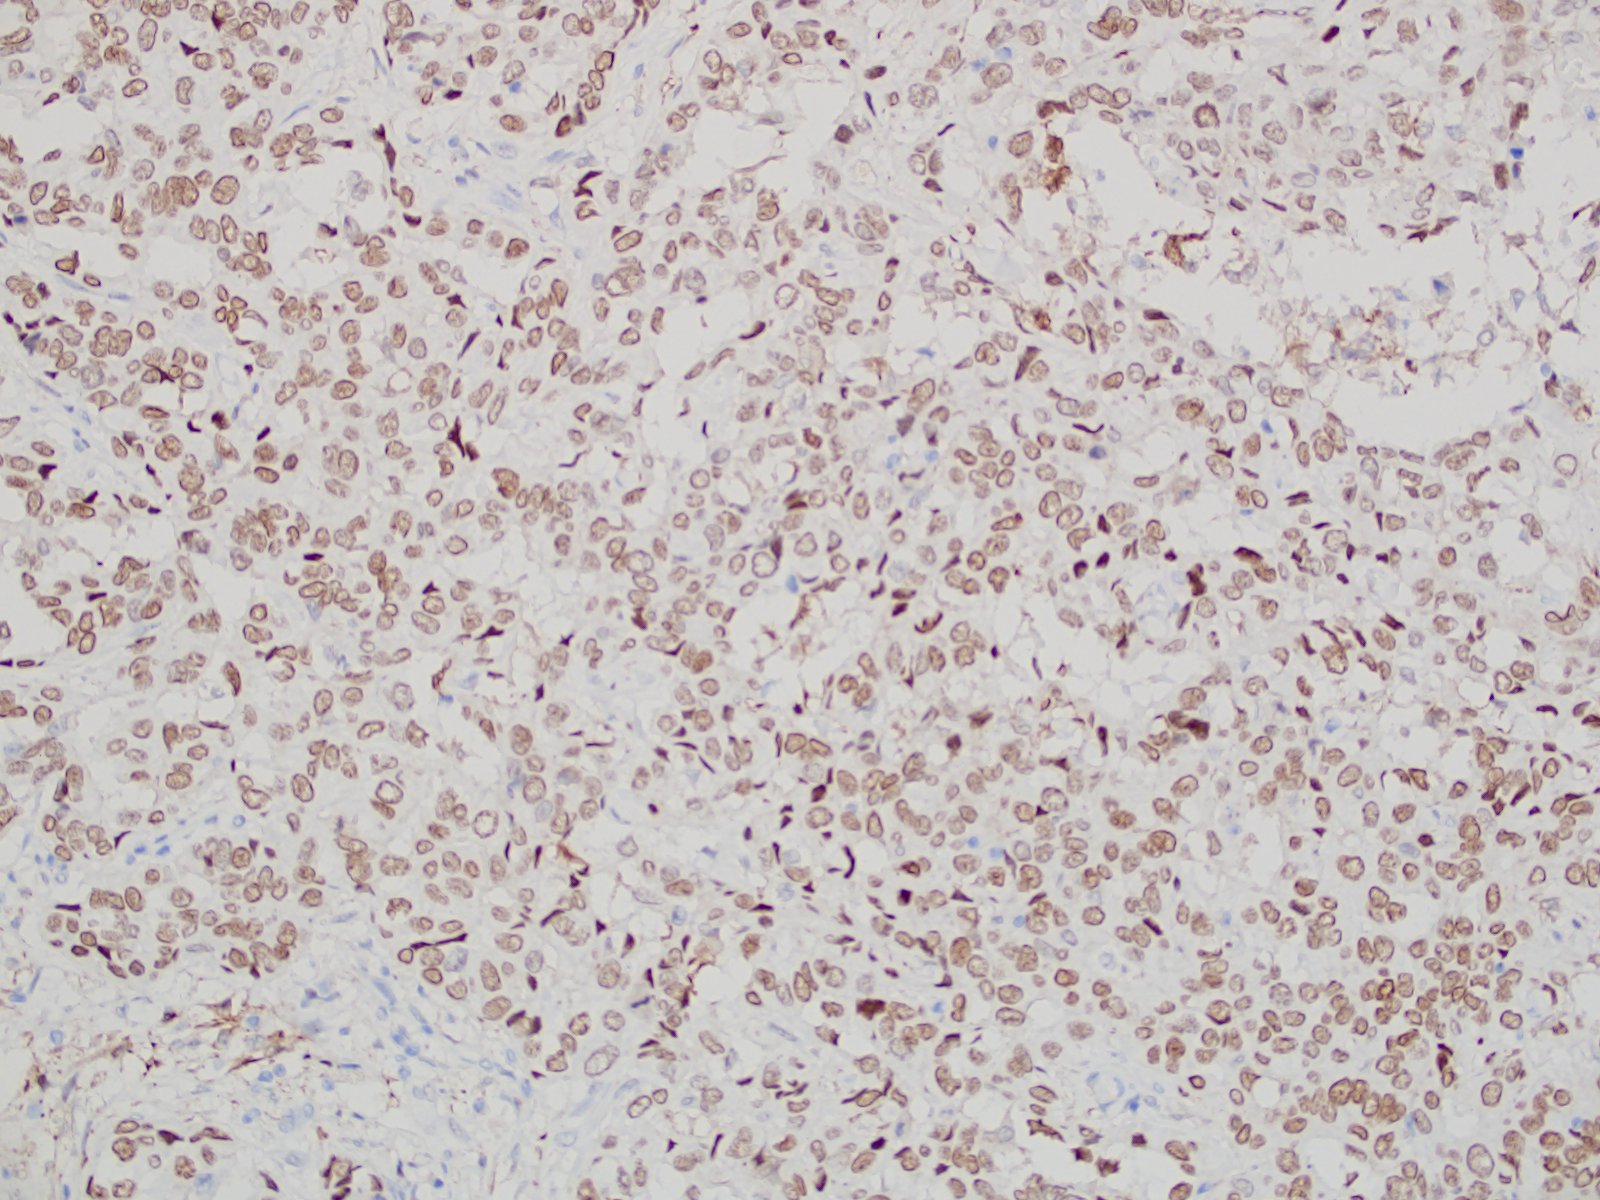

【新品单抗】TRPS1

单克隆兔抗人TRPS1

TRPS1属于GATA转录因子家族,位于人类染色体8q23-24中,起着核锌指蛋白的作用。TRPS1在多种人类实体恶性肿瘤中存在异常表达,其编码蛋白在不同肿瘤组织中呈现出了特异性表达,且表达水平因肿瘤的组织来源不同而存在差异。已有研究表明:TRPS1标记对所有类型乳腺癌均具有较好的特异性及敏感性,特别是对于三阴型乳腺癌。

| 克隆号 | 定位 | 阳性对照 | 修复条件 |

| EPR16171 | 细胞核 | 乳腺癌 | 高PH热修复 |